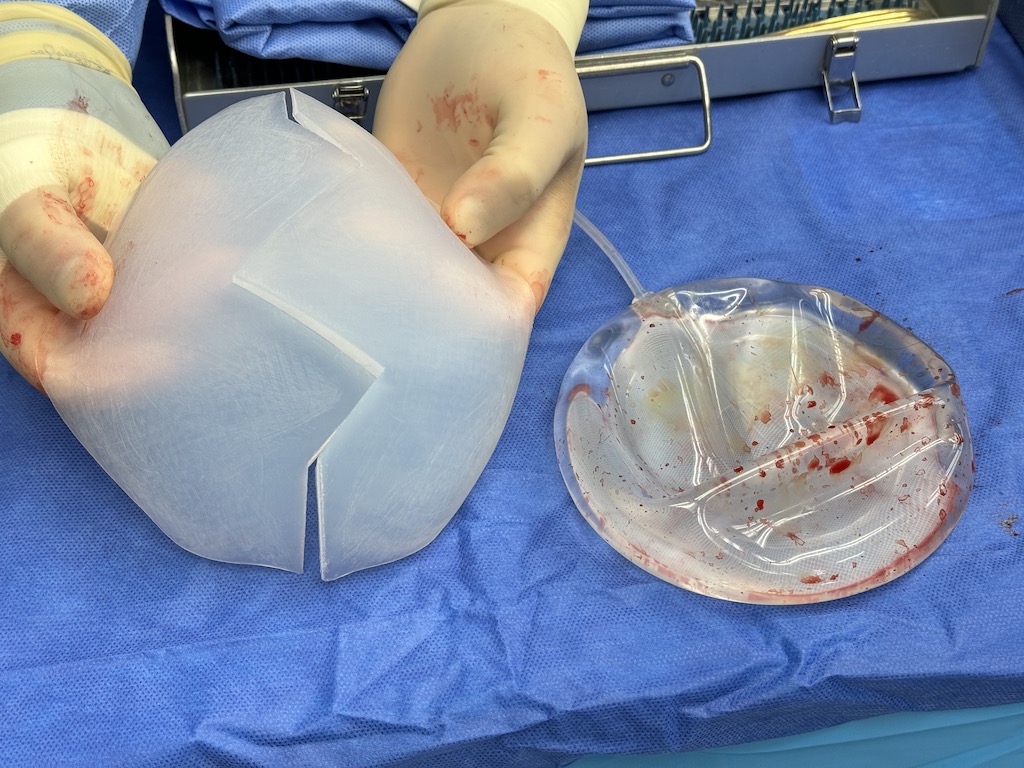

Patient 49

Desire for further skull augmentation after a primary skull implant.

Five years after an initial custom skull implant placement a new custom skull implant that increased the volume by 35% was placed.

Desire for further skull augmentation after a primary skull implant.

Five years after an initial custom skull implant placement a new custom skull implant that increased the volume by 35% was placed.